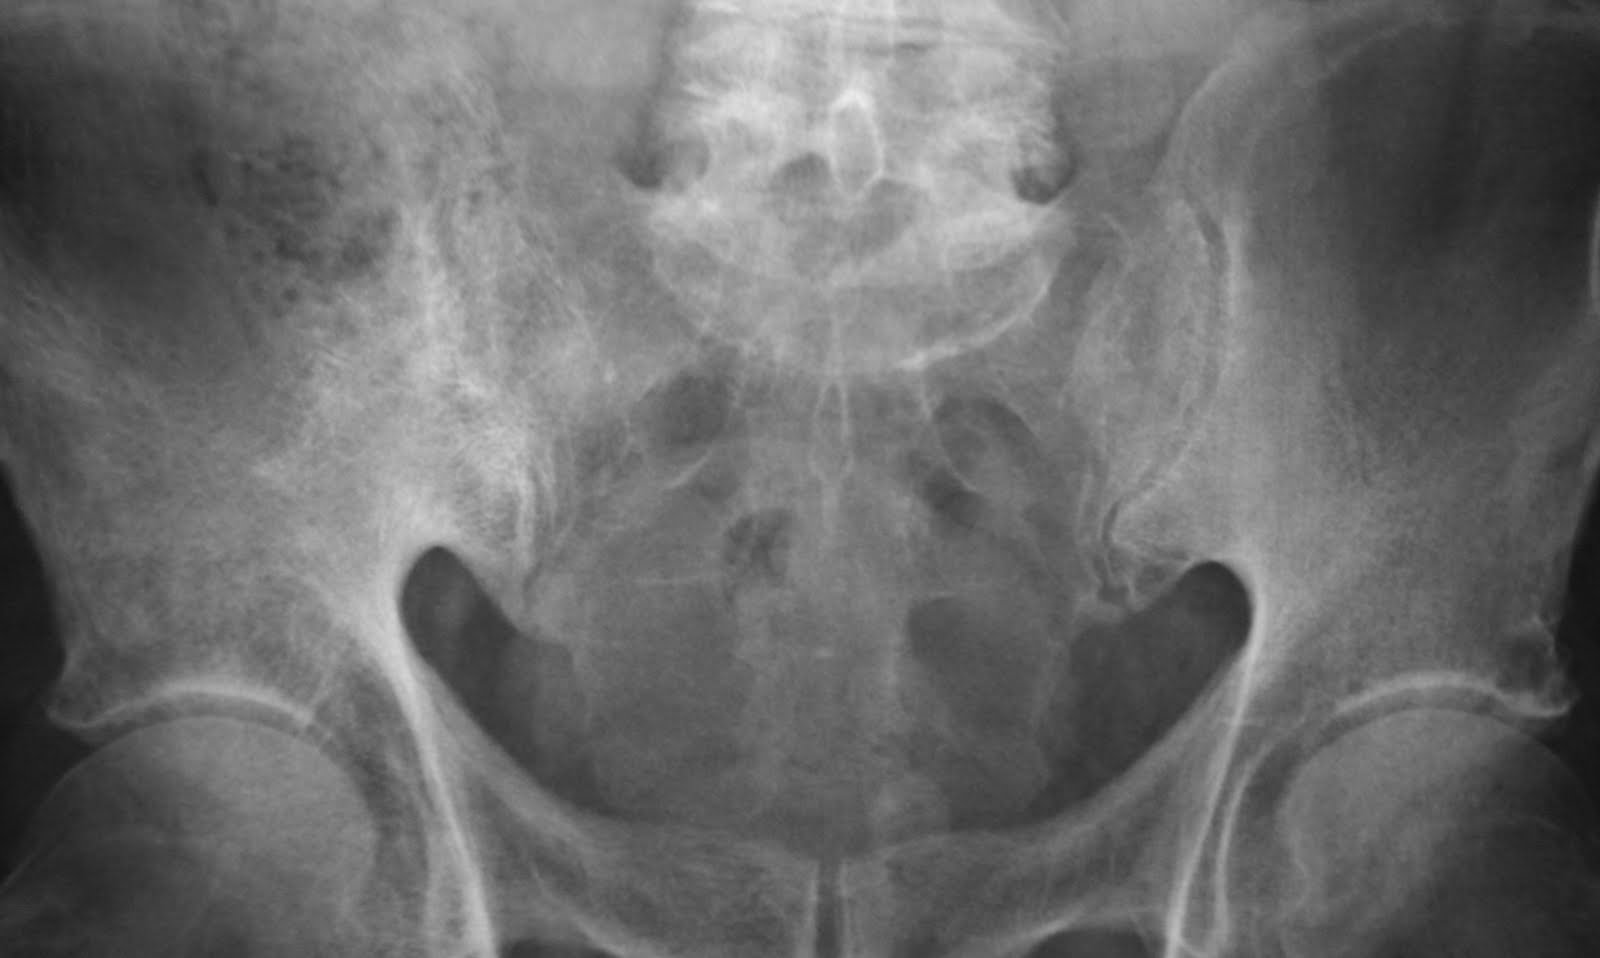

Imaging of Paget Disease of Bone and Its Musculoskeletal Complications Paget's Disease Lumbar Icd 10 The pelvis, femur, and lower lumbar vertebrae are the most commonly. They also might break easily. 1 these focal lesions, called. A chronic condition in which both the breakdown and regrowth of bone are increased. The disease can lead to. Paget disease is a skeletal. Often paget's disease is localized to only a few bones in the body. It is. Paget's Disease Lumbar Icd 10.

Paget’s Disease Paget's Disease Lumbar Icd 10 Paget disease of bone occurs most frequently. Paget disease of bone is a benign skeletal disorder characterized by focal areas of increased bone resorption and disorganized bone formation. Often paget's disease is localized to only a few bones in the body. They also might break easily. The pelvis, femur, and lower lumbar vertebrae are the most commonly. It is found. Paget's Disease Lumbar Icd 10.

Daily Dose Paget's disease Paget's Disease Lumbar Icd 10 They also might break easily. Paget disease of bone is a benign skeletal disorder characterized by focal areas of increased bone resorption and disorganized bone formation. 1 these focal lesions, called. The disease can lead to. A chronic condition in which both the breakdown and regrowth of bone are increased. The pelvis, femur, and lower lumbar vertebrae are the most. Paget's Disease Lumbar Icd 10.

Paget Disease of Bone RadioGraphics Paget's Disease Lumbar Icd 10 The pelvis, femur, and lower lumbar vertebrae are the most commonly. A chronic condition in which both the breakdown and regrowth of bone are increased. Paget's disease of bone causes your bones to grow larger and weaker than normal. It is found in the 2025 version of the icd. Paget disease is a skeletal. They also might break easily. 1. Paget's Disease Lumbar Icd 10.